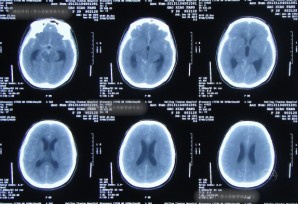

患者于2013年11月4日,突发剧烈头痛,难以忍受,前往北京某三甲医院进行头颅CT示蛛网膜下腔出血(图-1),随即进行头颅CTA检查确诊为右前交通动脉瘤(图-2)。

图-1:2013年11月4日